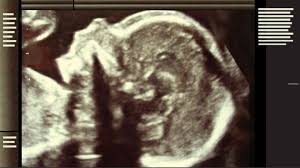

Schwanger und der Vater will das Kind nicht.

Denn das muss wenn es nun mal da ist auch versorgt werden und es wäre ihm gegenüber ungerecht wenn man ihm den Unterhaltsanspruch an. Du erkennst die Vaterschaft noch während der Schwangerschaft. Von Gesetzeswegen kannst du aus drei Gründen Vater werden. SSW Ungewollt schwanger Vater will das Kind nicht Typ 1 Diabetes. Selbst wenn ein Vater der das Kind nicht will darauf besteht dass die Frau die Pille danach nimmt dass die Frau abtreibt oder das Kind vertraulich entbindet wird er zum Unterhalt für das Kind verpflichtet wenn die schwangere Frau das Kind austrägt. Ungewollt schwanger er will dass ich abtreibe. Wenn das Kind innert sechs Monaten von keinem Mann anerkannt worden ist bekommt es einen Beistand dessen Aufgabe es ist die Vaterschaft zu klären. SSW Ungewollt schwanger Vater will das Kind nicht Typ 1 Diabetes Hartz 4 7. Die trauernummer mit dem kind kannst dir echt sparen.

Allerdings schreibst du so als gäbe es keine Entscheidung mehr zu treffen sondern nur noch den Schmerz und die Sorgen zu sortieren. Es ist eine schwere Situation und ein trauriges Gefühl wenn der Mann den man liebt Soetwas fordert. Schwanger doch mein Partner will das Kind definitiv nicht. Denn egal wer der Papa ist es ist ihr kind und bleibt ihr kind und hat es bereits jetzt lieb egal wie die Sache mit den Vätern zu Ende geht. Wenn man absolut kein Kind mehr will verhütet man doppelt zB. Ungewollt schwanger und der Vater will das Kind nicht. Wollt ihr das Kind oder wollt ihr einen Schwangerschaftsabbruch.